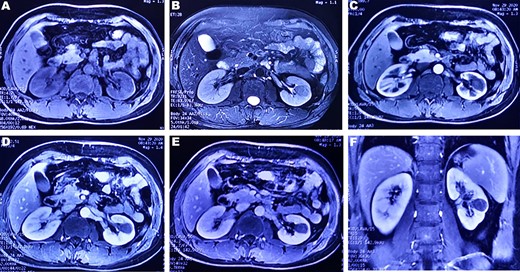

A 37-year-old male underwent a computed tomography scan (CT), which revealed a 2.5 × 1.9 cm slightly lower density ingrown mass in the lower pole of left kidney for 1 month. The patient was asymptomatic and had a history of kidney stones. The shape of the mass was regular, with unclear boundaries. Enhanced CT showed that the enhancement of the mass was lower than that of the surrounding renal parenchyma (Fig. 1). On magnetic resonance imaging (MRI), a circular abnormal signal was detected in the cortical medullary area of left kidney, with an equal signal on T1WI and a slightly low signal on T2WI (Fig. 2A and B). The enhanced MRI scan showed no obvious enhancement in the cortical and medullary phases and a slightly dotted high signal in the excretion phase (Fig. 2C–F). The mass was a space-occupying ingrown lesion with insufficient blood supply. Patients underwent laparoscopic partial nephrectomy and received no postoperative therapy. After the tumor was incised, a 2.3 × 2 cm soft mass that was grayish-white and slightly grayish-yellow was found with clear boundary. Histology (hematoxylin and eosin staining) results showed that the tumor was composed of elongated tubules arranged in parallel. The tubules lined with cuboid and spindle cells set in a small amount of myxoid matrix (Fig. 3A). Most of the tumor cells were round, a few were spindle and elliptical, with eosinophilic nucleoli. Mitotic figures were rare and the atypia is not obvious. Obvious foamy macrophage aggregates could be seen in some areas (Fig. 3B). Immunohistochemical results were as follows: CK7(+), P504S (+), PAX-8(+), CD10(−) (Fig. 3C–F). The Ki67 stain showed proliferation rates up to 5%. The pathological result demonstrated left renal mucin-poor MTSCC. We performed next-generation sequencing (NGS) for case, and the result showed that the tumor mutational burden was 2.74 mutation/Mb. RET gene mutation was considered as a mutation of uncertain significance. The detection of multiple genetic polymorphism sites of tumors shows that it may be slightly sensitive to some chemotherapeutics like gemcitabine. PD-1/PD-L1 immunotherapy may not benefit the patient. The patient was followed up for 8 months after surgery. No evidence of metastasis or recurrence was found.

(A and B) A round-like abnormal signal can be seen in the cortex and medulla of the left kidney, which is equal signal on T1WI and slightly low signal on T2WI; (C–E) In the arterial phase, parenchymal phase and venous phase of enhanced MRI, a heterogeneous, progressive and slow enhancement is noted. (F) Enhanced arterial phase of coronary T1WI showed a low signal mass located in the lower pole of the left kidney.

MTSCC was classified into ‘classic’ and ‘mucin-poor’ based on the proportion of interstitial mucin in histology [4]. Few studies individually described the imaging characteristics of mucin-poor MTSCC. In all phases of enhanced CT, the mean attenuation of MTSCC tumor was not only less than the normal renal cortex and medulla, but also less than collecting duct carcinoma [5–7]. The tumors presented homogeneous pattern enhancement and were usually small (≤5 cm) [6]. In MRI scans, the T1WI signal was isointense to normal renal parenchyma. T2WI signal was usually diverse, including hypo-, iso- and hyperintensity [5]. In our study, tumors presented low-signal intensity on T2w images. This may be related to no mucinous or myxoid stroma. It may be a significant feature to distinguish mucin-poor MTSCC and classic MTSCC on imaging diagnosis.